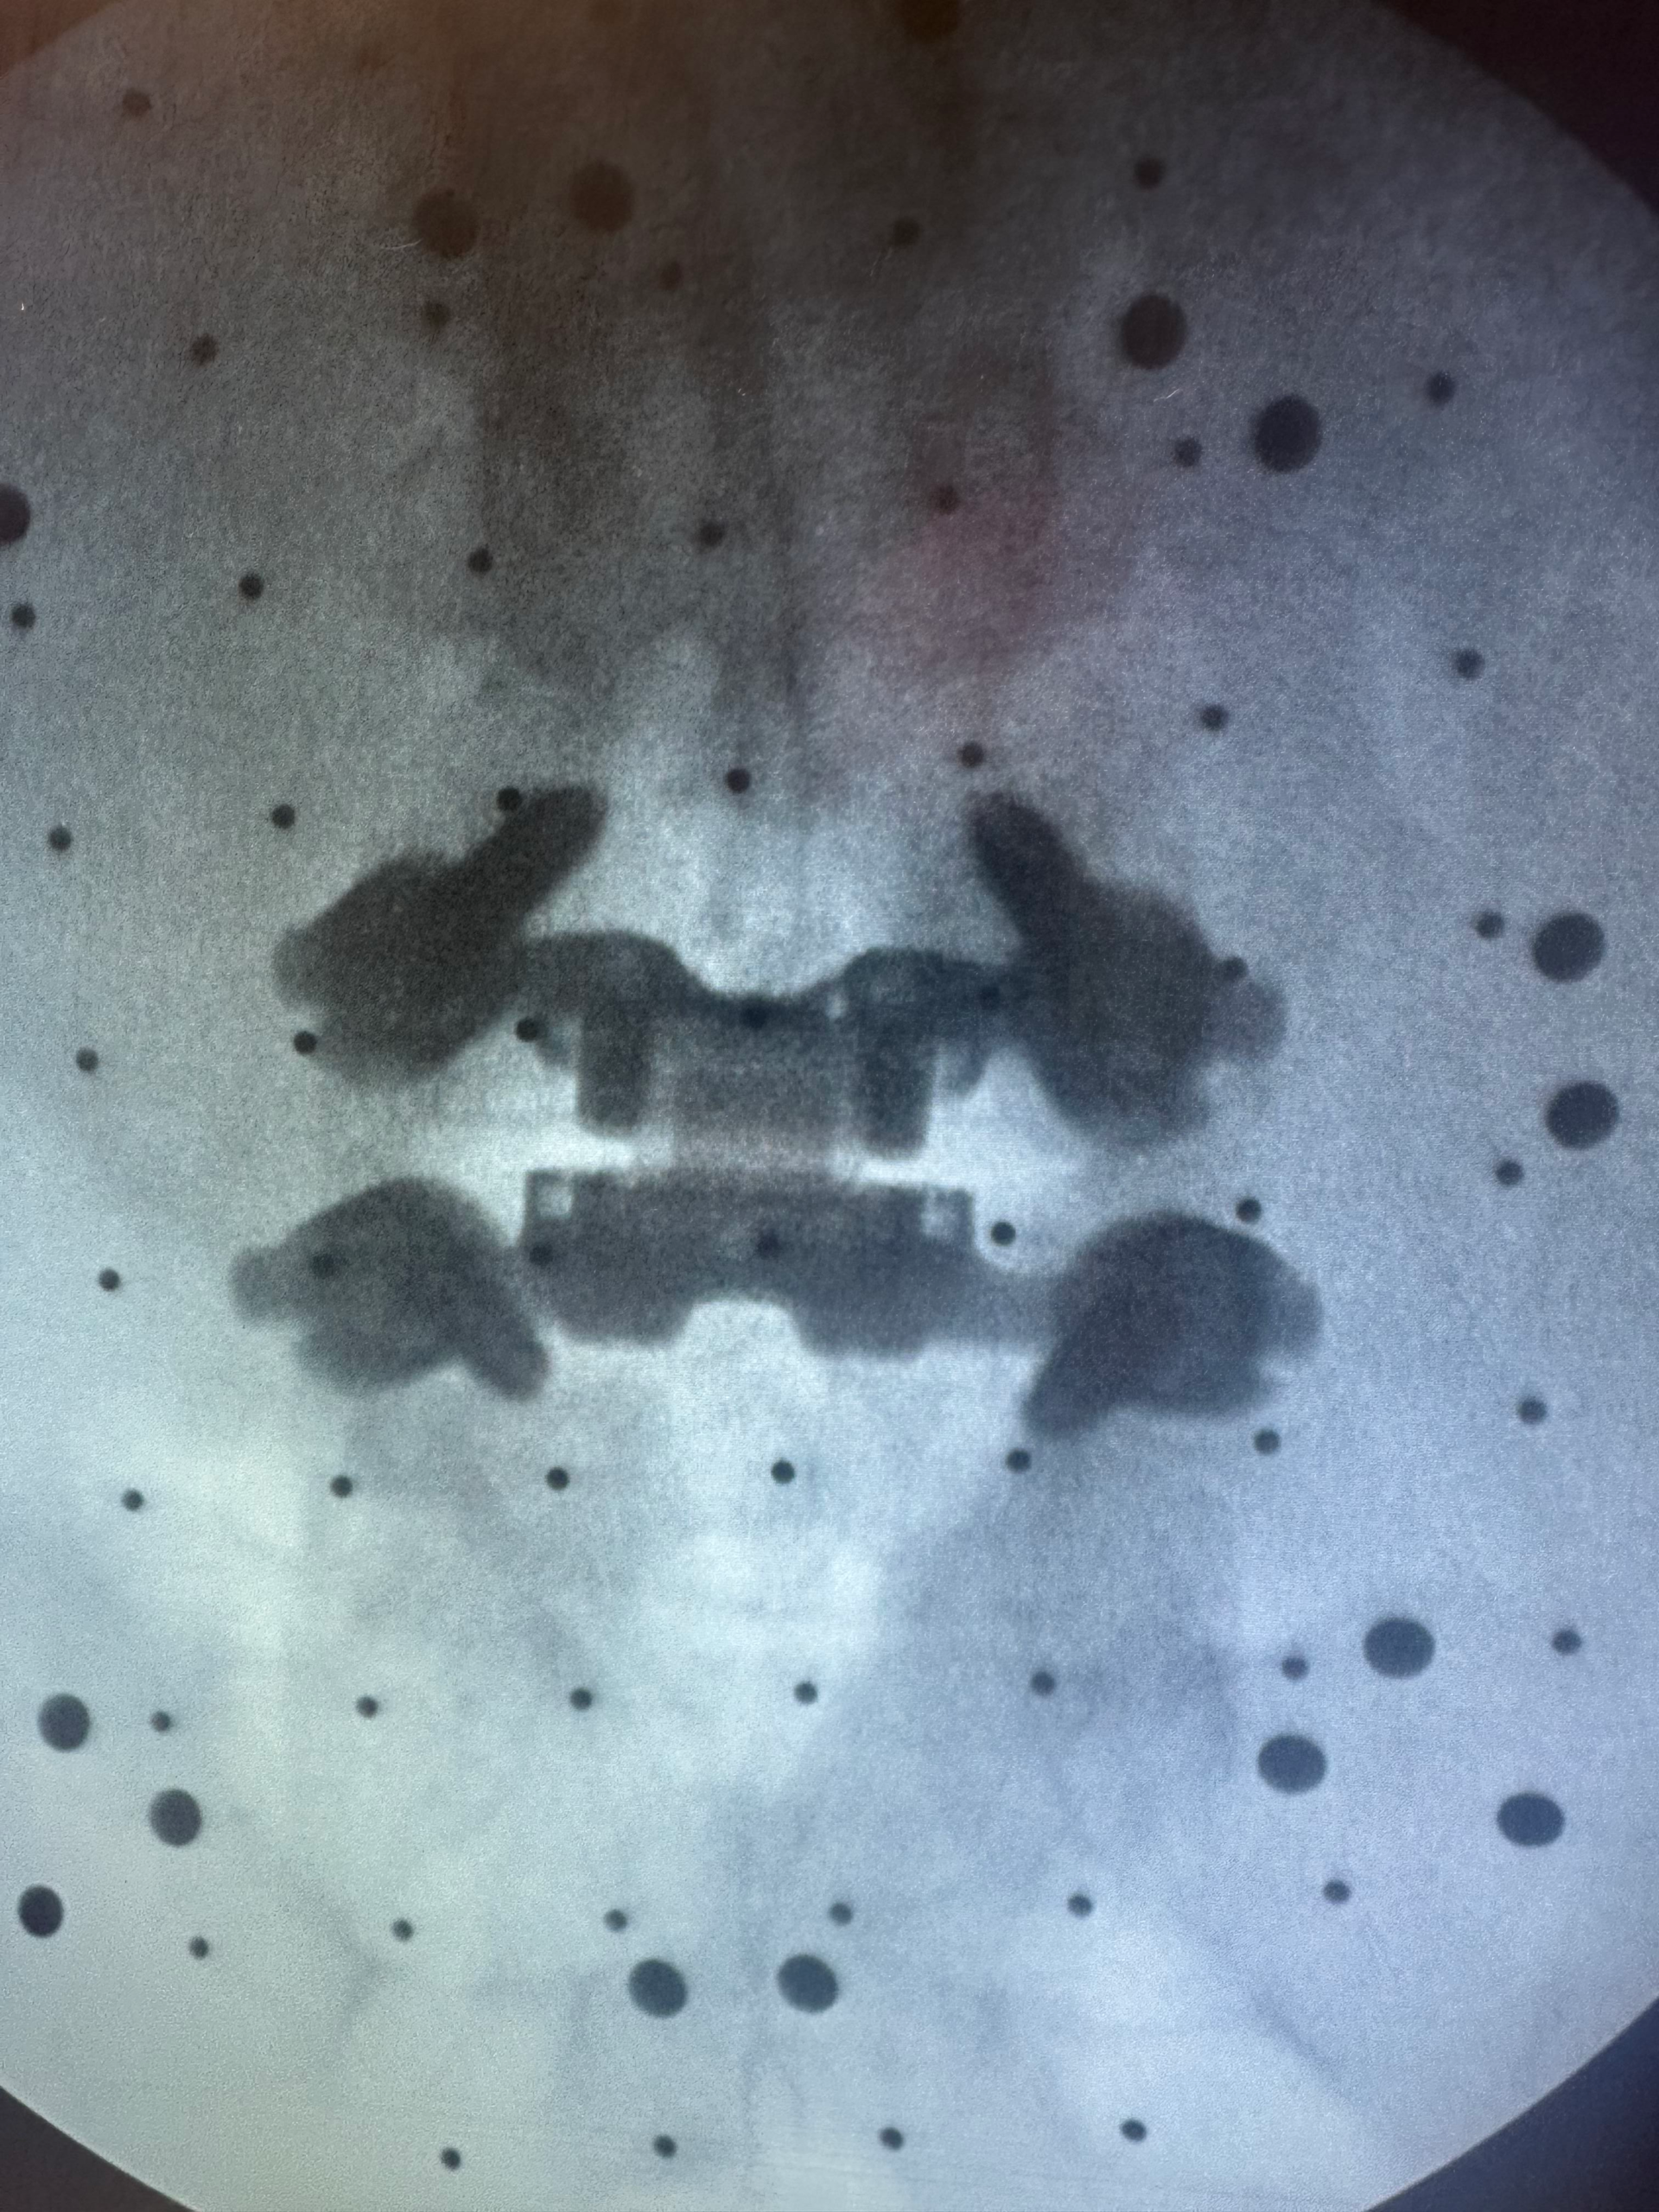

Lumbar disc replacement

Lumbar disc replacement

- TOPS Procedure with robotic guidance